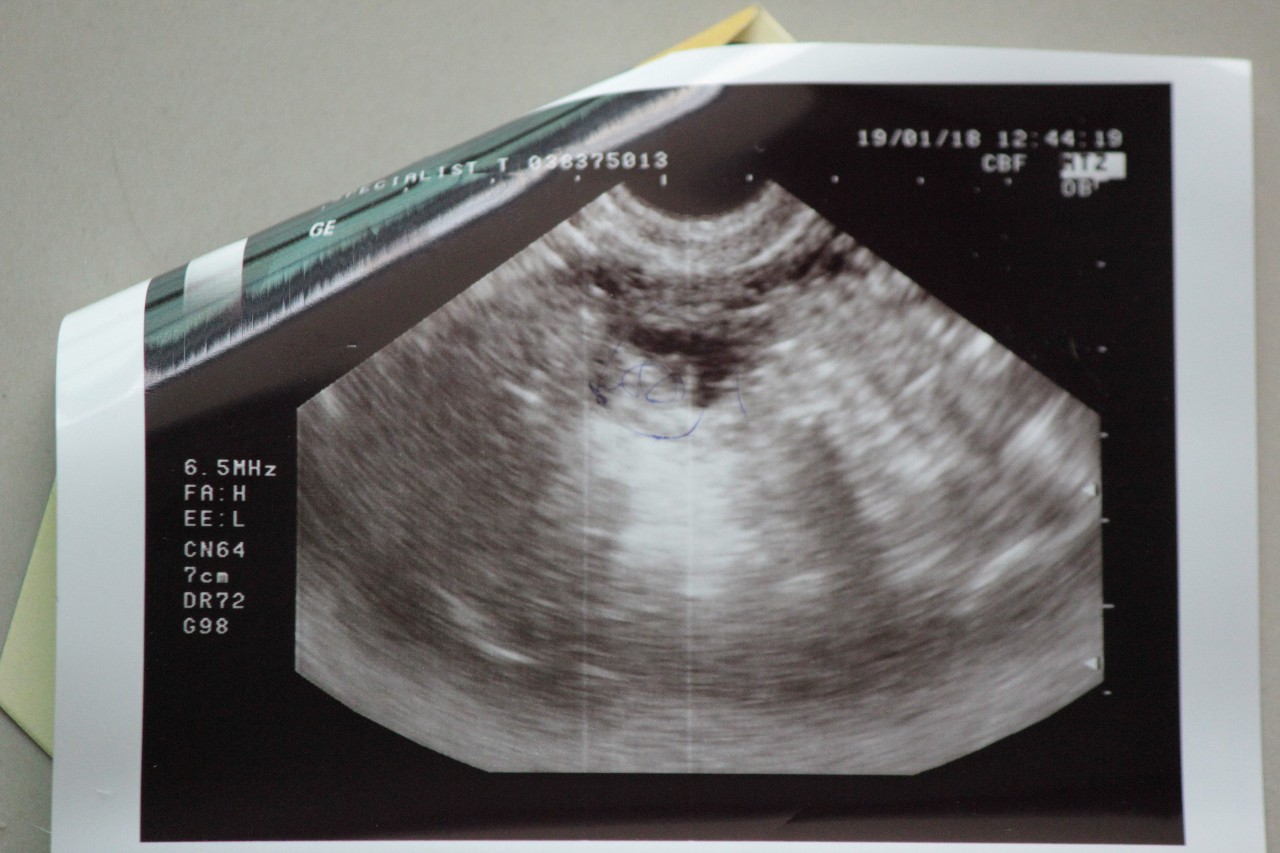

Желтое тело на УЗИ

Желтое тело можно обнаружить во время диагностической процедуры, если УЗИ пришлось на период сразу после овуляции. Это подтверждает, что цикл овуляторный и сама овуляция прошла нормально.

Желтое тело можно увидеть на трансабдоминальном и трансвагинальном УЗИ органов малого таза. Для женщин, живущих половой жизнью, более точным вариантом будет трансвагинальное исследование.

На экране аппарата врач УЗИ увидит неоднородное округлое образование. Появляется желтое тело в правом или левом яичнике в зависимости от локализации созревания доминантного фолликула и овуляторной яйцеклетки. Сторона созревания не имеет принципиального значения для будущей беременности и здоровья женщины.